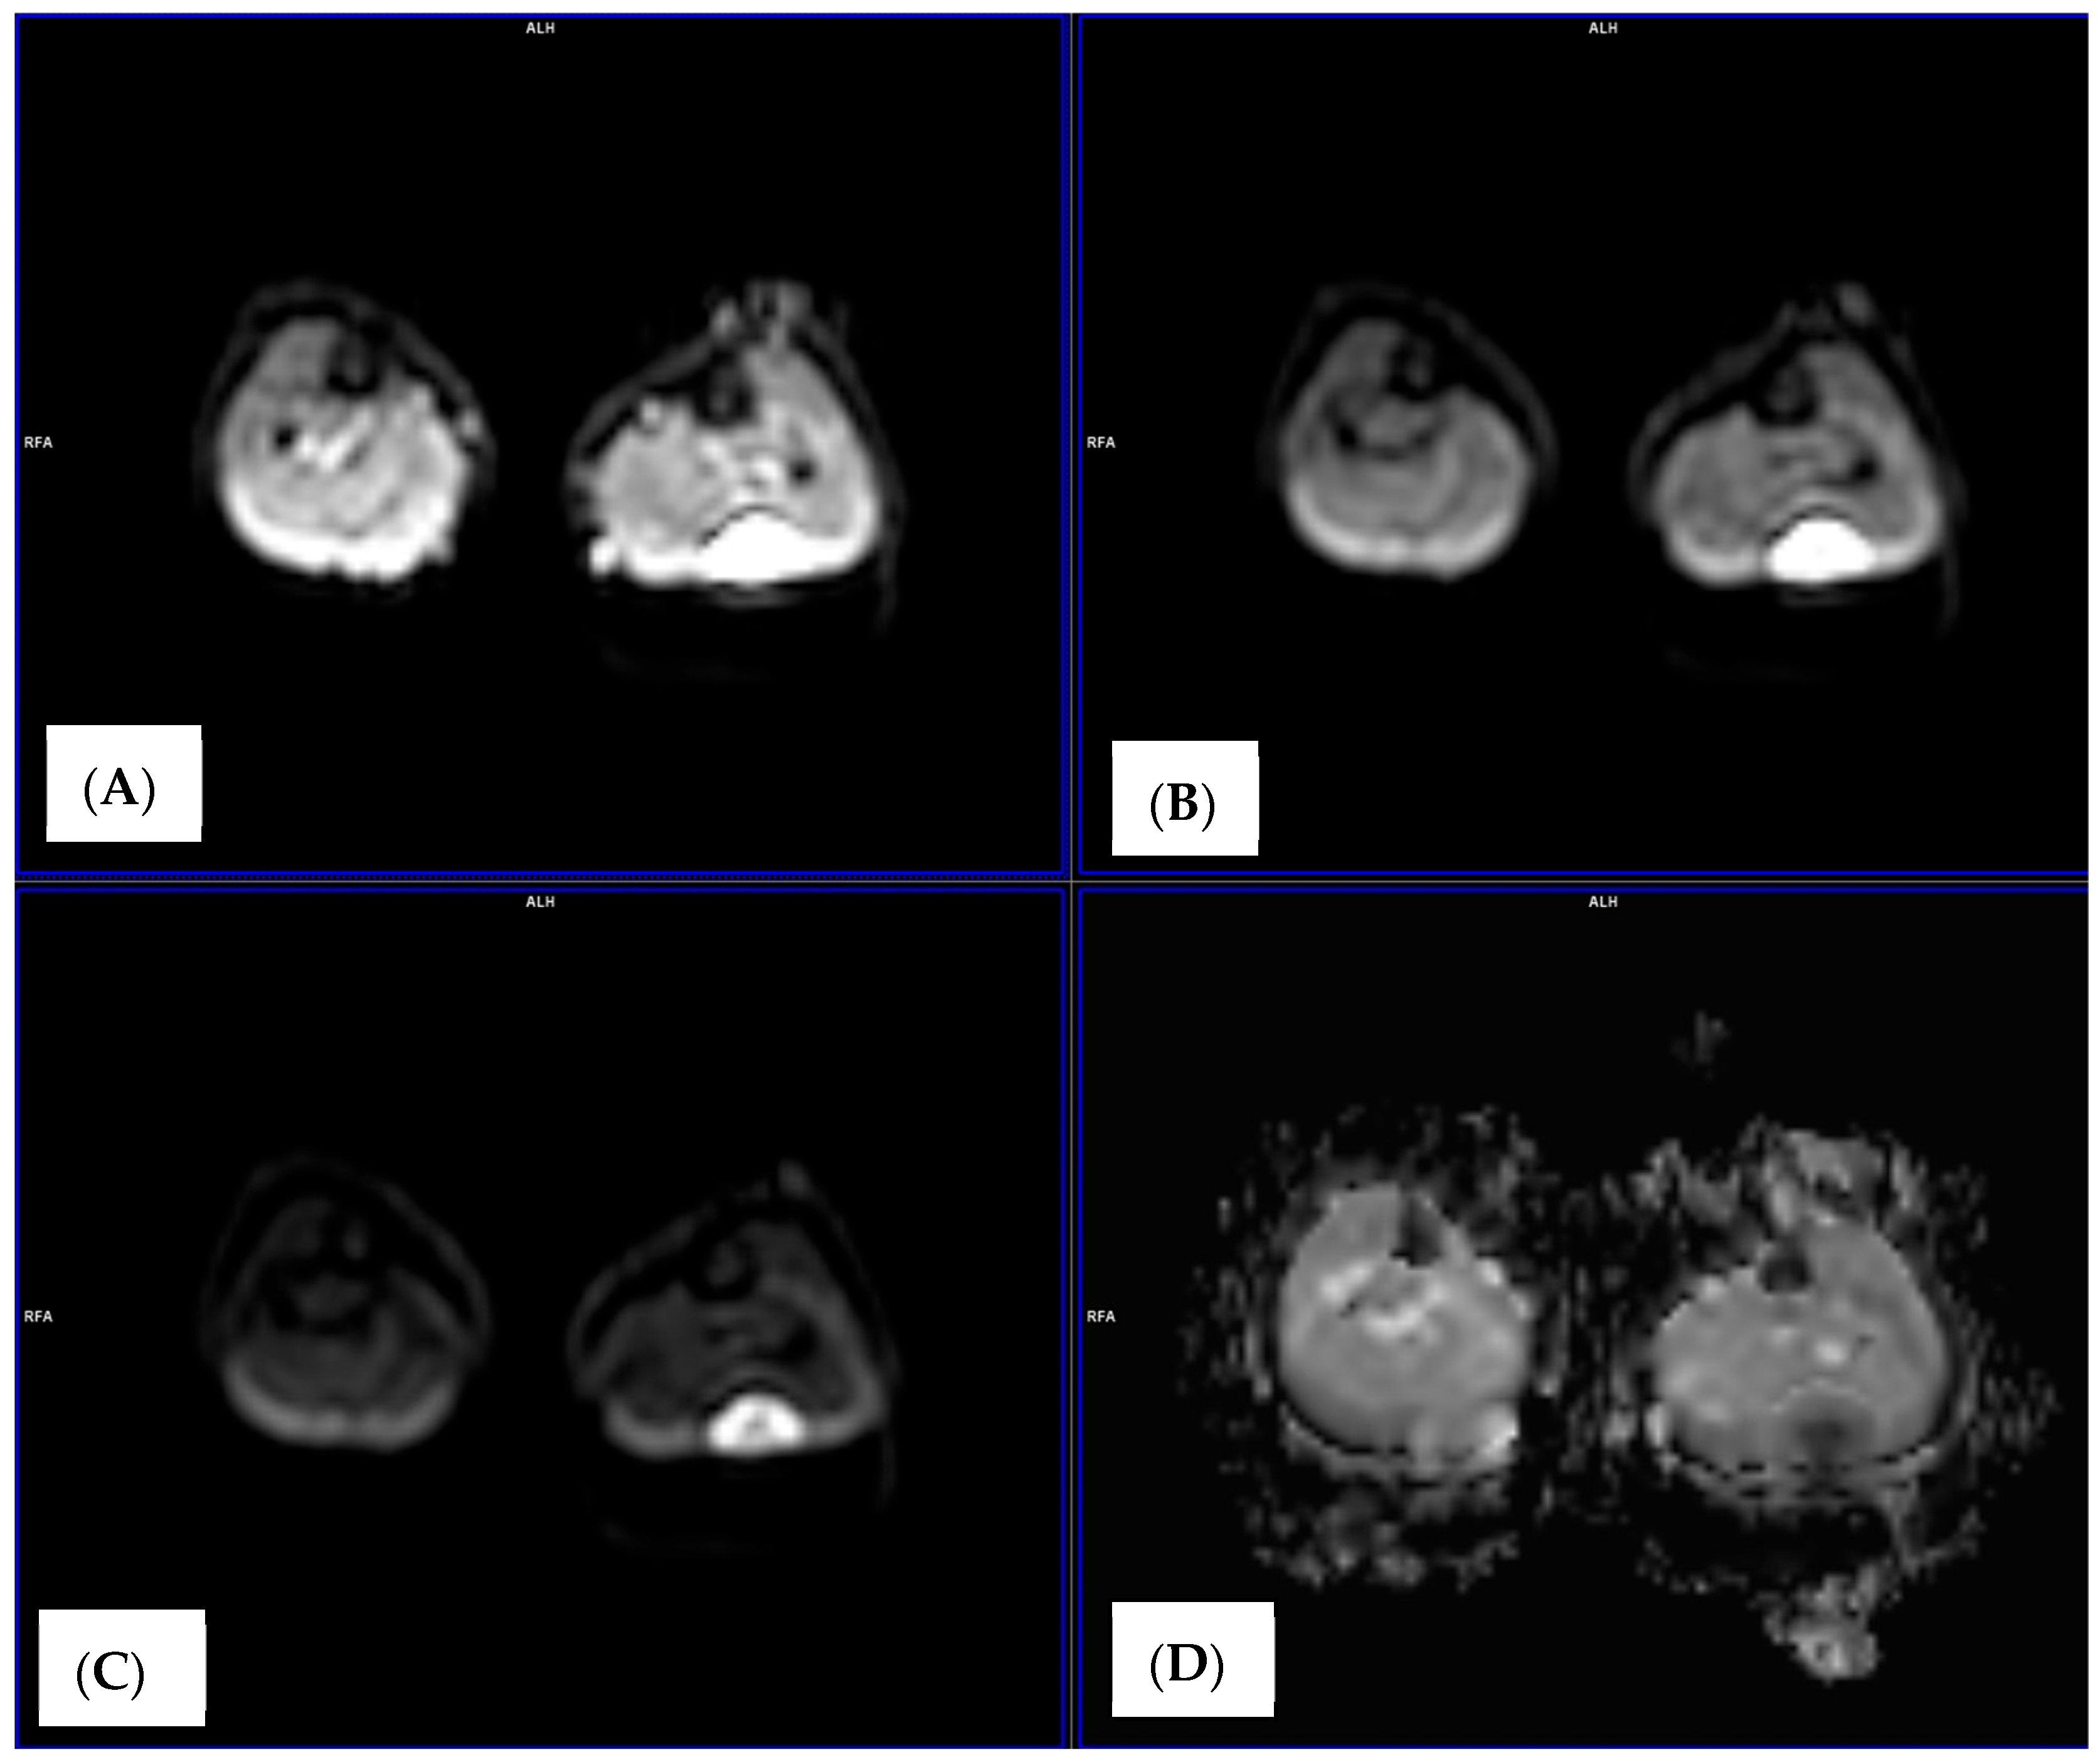

2.4. Image Analysis and ADC Measurements

3.1. Baseline Diffusion Characteristics

3.2. ADC Changes After Chemotherapy